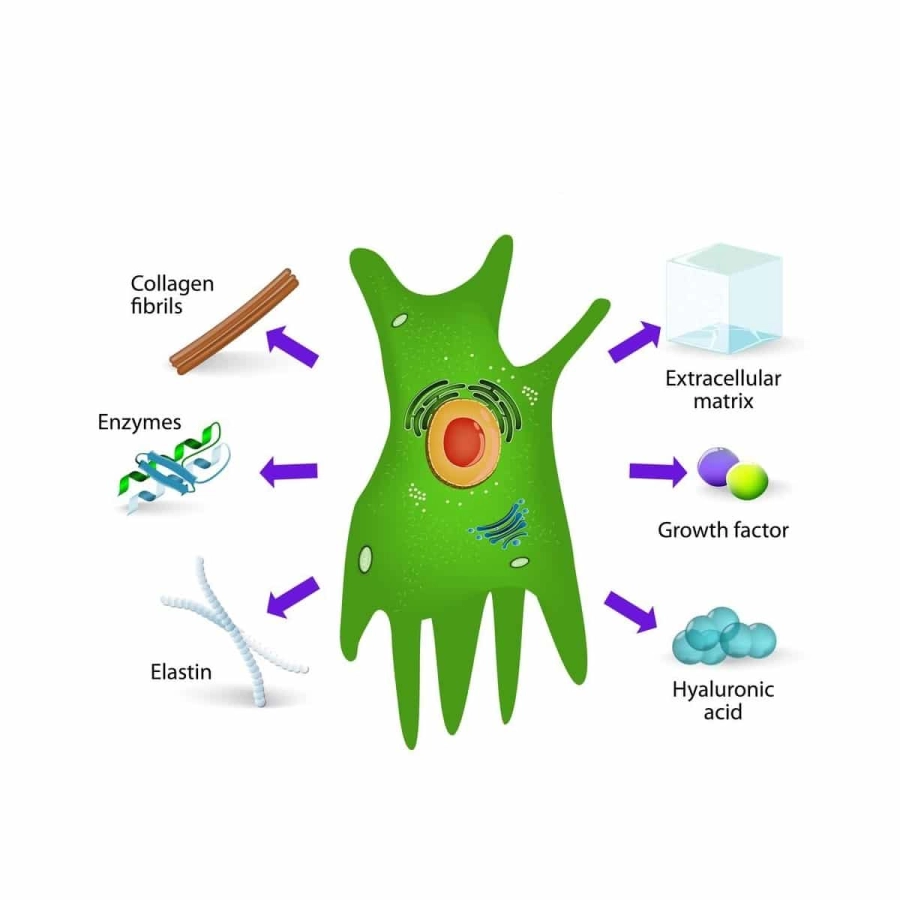

Генетики тоже добавляют сложных штрихов в картину: они установили, что у человека тоже есть гены, позволяющие широкую регенерацию. Как раз у эмбриона они еще работают, а после — напротив, принудительно отключаются организмом. Например, таковы сигнальные системы белков WNT, BMP (кодирует белки костных морфогенетических белков) и FGF (кодирует передний телэнцефалический источник факторов роста фибробластов). Фибробласты — клетки соединительной ткани человека, они играют ключевую роль в заживлении ран. Почему после восьми недель все это выключается?

Фибробласты в послеэмбриональной стадии играют ключевую роль в заживлении ран человека. Форма их может быть довольно разной, от веретенообразной до звездчатой, но функции похожи: такие клетки массово вырабатывают белки «на экспорт», в помощь восстановлению окружающих тканей / © Wikimedia Commons